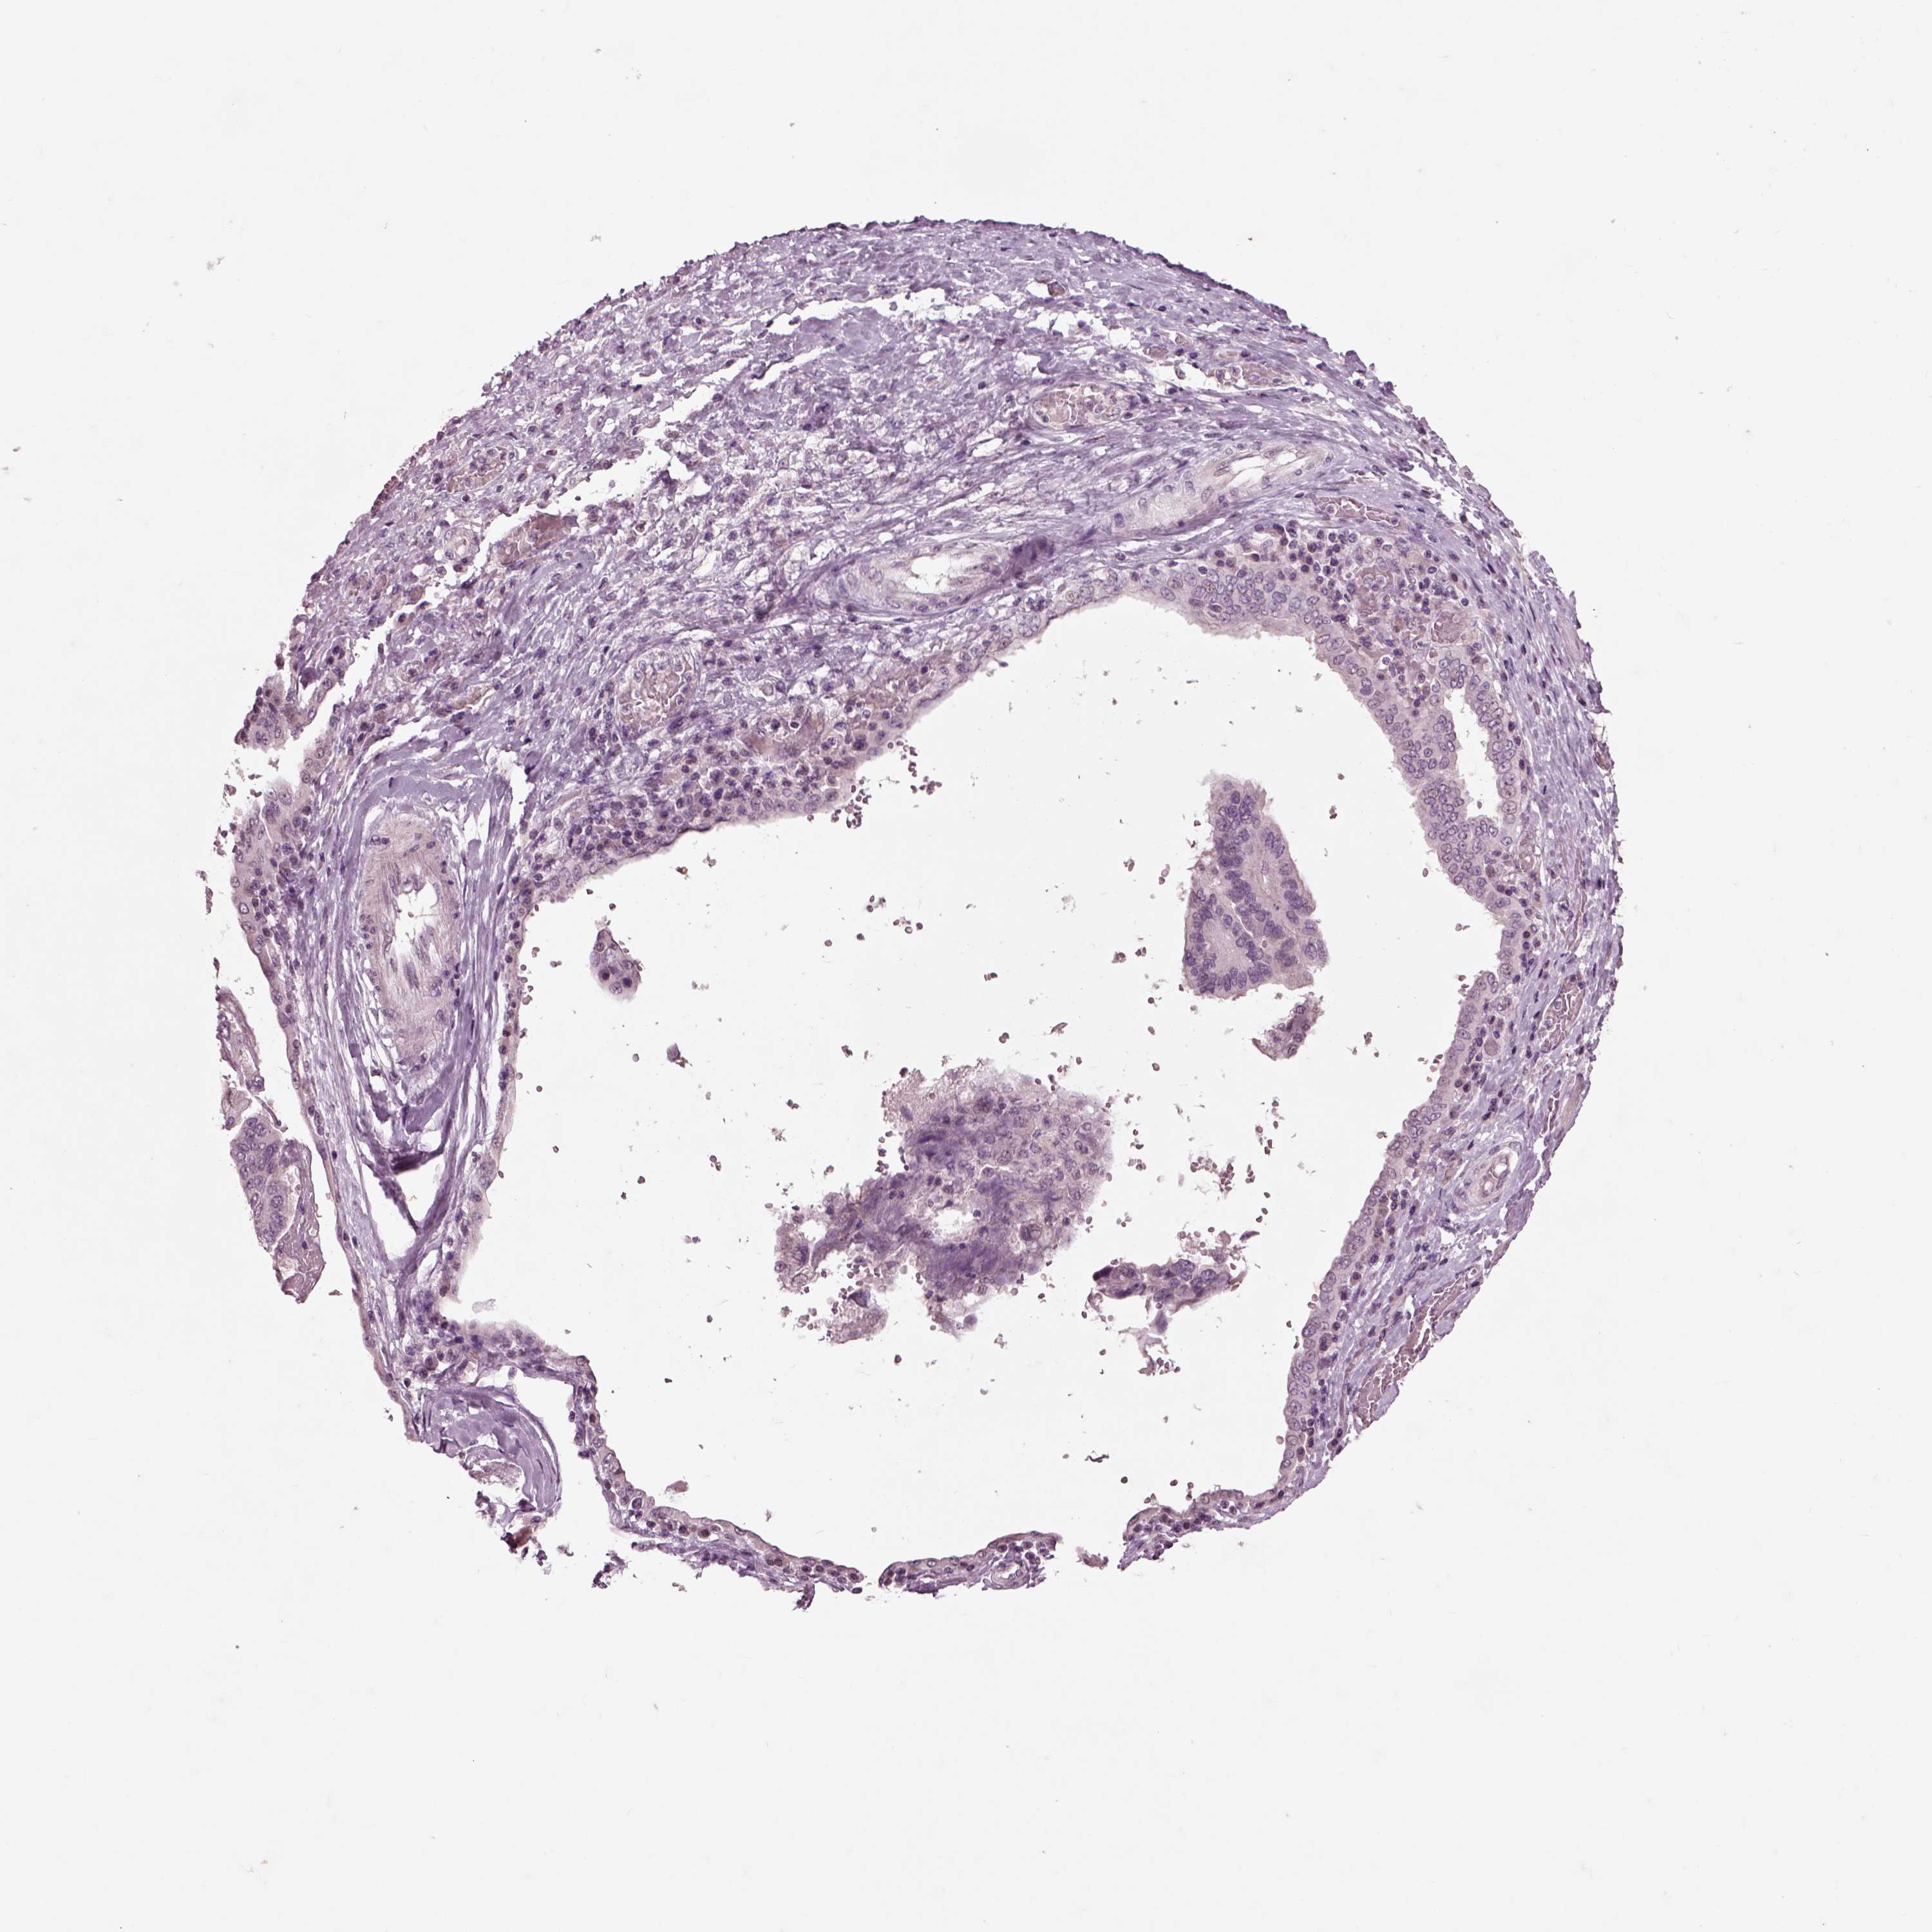

OVARIAN CANCER - Protein expressioni

A mouse-over function shows sample information and annotation data. Click on an image to view it in a full screen mode. Samples can be filtered based on level of antibody staining by selecting one or several of the following categories: high, medium, low and not detected. The assay and annotation is described here.

Note that samples used for immunohistochemistry by the Human Protein Atlas do not correspond to samples in the TCGA dataset.

Antibody stainingi

Antibody staining in the annotated cell types in the current human tissue is reported as not detected, low, medium, or high, based on conventional immunohistochemistry profiling in selected tissues. This score is based on the combination of the staining intensity and fraction of stained cells.

Each image is clickable and will lead to virtual microscopy that enables deeper exploration of all samples and also displays staining intensity scores, fraction scores and subcellular localization as well as patient and tissue information for each sample.

Antibody HPA008759

Cystadenocarcinoma, serous, NOS